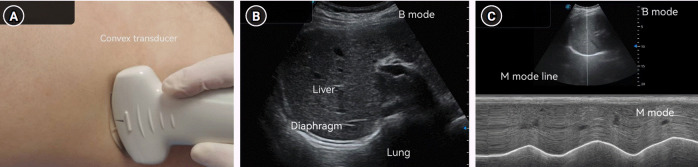

Methods: This study included 246 patients undergoing the spontaneous breathing trial. Diaphragmatic function was evaluated by ultrasound, including the diaphragm thickness at the end of calm breathing (thickness of the diaphragm at functional residual capacity [TdiFRC]) and the maximum diaphragm thickness at the end of inspiration (thickness of the diaphragm at full vital capacity [TdiFVC]); TF=(TdiFVC-TdiFRC)/TdiFRC×100%. DM, the oxygenation index (the ratio of the partial pressure of arterial oxygen to the fraction of inspired oxygen), and the rapid shallow breathing index (RSBI) were measured.